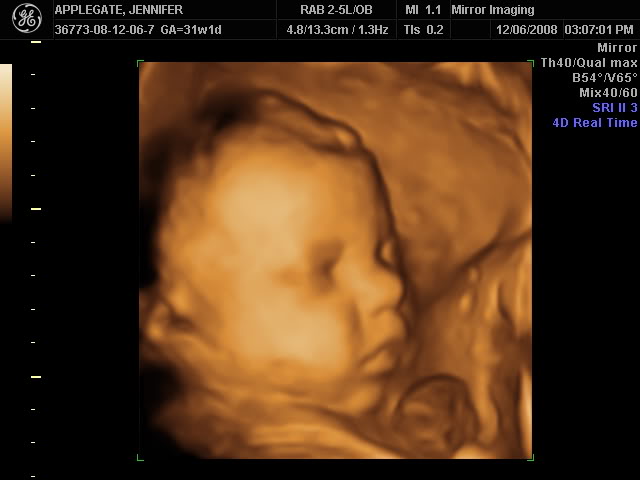

3D/4D ultrasound at 30 weeks 5 days. The place said they don't do it after 32 weeks. Below is a breakdown on what to expect during an ultrasound depending on how many weeks pregnant you are:.

At 30 weeks, a baby is around 10 3/4 inches (27.4 centimeters) from the top of their head to the bottom of their buttocks (known as the crown-rump length), and baby's height is about 15 1/4 inches (38.9 centimeters) from the top of their head to their heel (crown-heel length). Room is big enough to seat the whole family. The sonographer switched between black and white 2D images and the brown 3D images, making a 4D recording of the little movement that Sticky Bean did produce.

Pregnancy week 30- a 4D ultrasound scan. Peek A Belly 3D Inc. By 30 weeks, my son was in position for delivery.

Not all women have an ultrasound around the 30-week mark, but some providers order a scan to check growth and development. It is recommended that you have an ultrasound between 18 to weeks. Because your baby's facial features are more developed and he can actually open his eyes inside, your ultrasound will be a close likeness of what he'll look like once he's born.